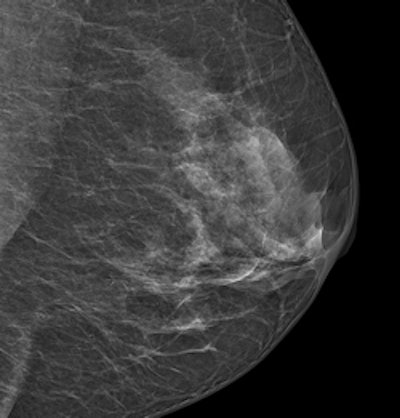

An image acquired with Philips' MicroDose SI system. Image courtesy of Philips.

MicroDose SI uses digital photon-counting technology, which allows clinicians to conduct exams using low radiation dose without compromising image quality; the company received 510(k) clearance from the FDA for the device in February.

High breast density is a known risk factor for breast cancer, and interpretation of mammograms of dense breast tissue is more difficult. Philips' breast density software is the first application the company has developed to interpret the spectral data obtained from MicroDose SI by giving radiologists a density score that works with BI-RADS classifications, according to the company.